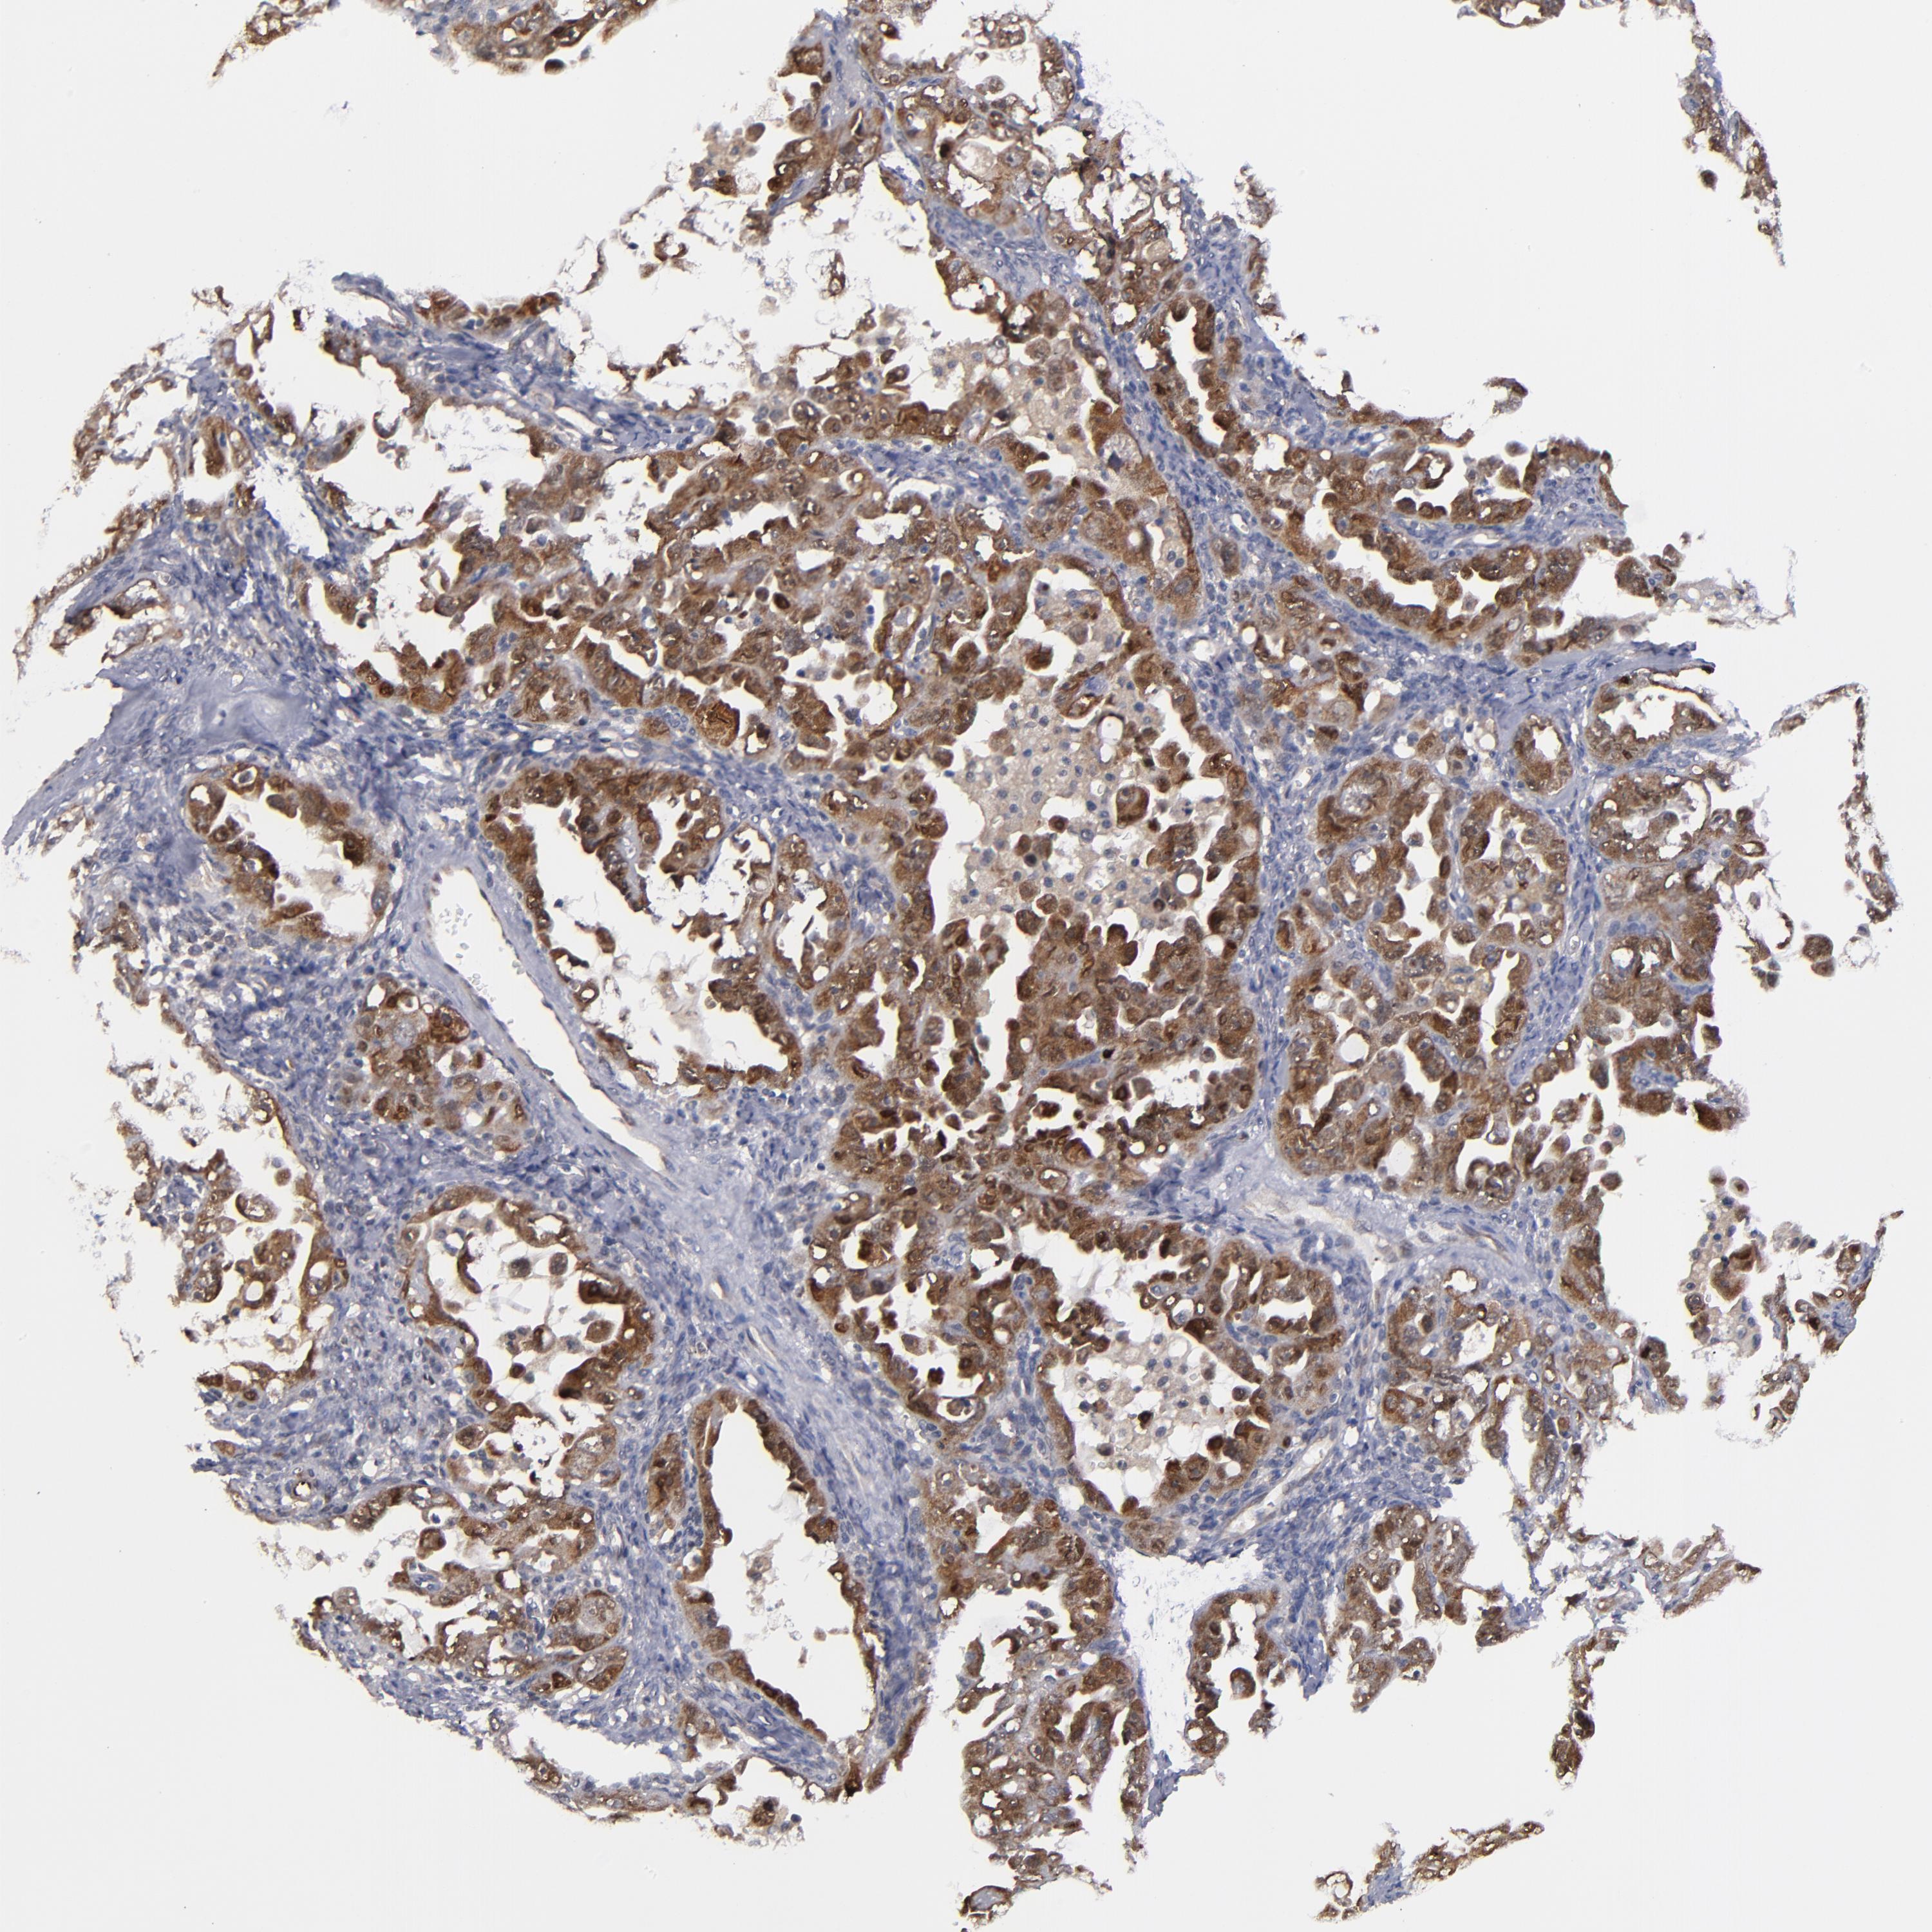

OVARIAN CANCER - Protein expressioni

A mouse-over function shows sample information and annotation data. Click on an image to view it in a full screen mode. Samples can be filtered based on level of antibody staining by selecting one or several of the following categories: high, medium, low and not detected. The assay and annotation is described here.

Note that samples used for immunohistochemistry by the Human Protein Atlas do not correspond to samples in the TCGA dataset.

Antibody stainingi

Antibody staining in the annotated cell types in the current human tissue is reported as not detected, low, medium, or high, based on conventional immunohistochemistry profiling in selected tissues. This score is based on the combination of the staining intensity and fraction of stained cells.

Each image is clickable and will lead to virtual microscopy that enables deeper exploration of all samples and also displays staining intensity scores, fraction scores and subcellular localization as well as patient and tissue information for each sample.

Antibody HPA002853

Staining

High

Medium

Low

Not detected

Intensity

Strong

Moderate

Weak

Negative

Quantity

>75%

75%-25%

<25%

None

Location

Nuclear

Cytoplasmic/membranous

Cytoplasmic/membranous,nuclear

Cystadenocarcinoma, serous, NOS

Cystadenocarcinoma, mucinous, NOS

Carcinoma, endometroid